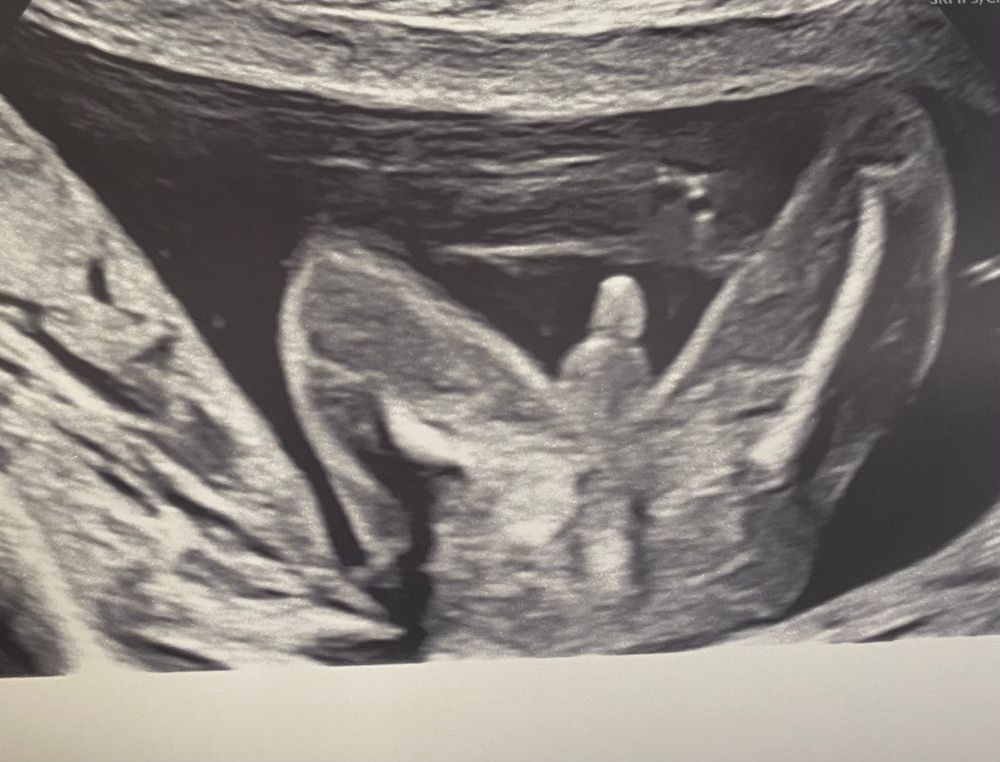

Ой девочки, хохотала после второго скрининга до слёз. В 17 недель делали цервикометрию и врач сказала, что чётко видит пол. Историю об мини «гендер-пати» писала в дневнике. Пришла я на прошлой неделе на второй скрининг и решила уточнить. Спросила: «а точно мальчик?». Врач улыбнулась, показала мне на экран и сказала: «Точно! Сами смотрите! Я вам даже фото такое сделаю». Теперь у меня есть такое фото с узи:

Так сказать наглядное подтверждение 😂😂😂